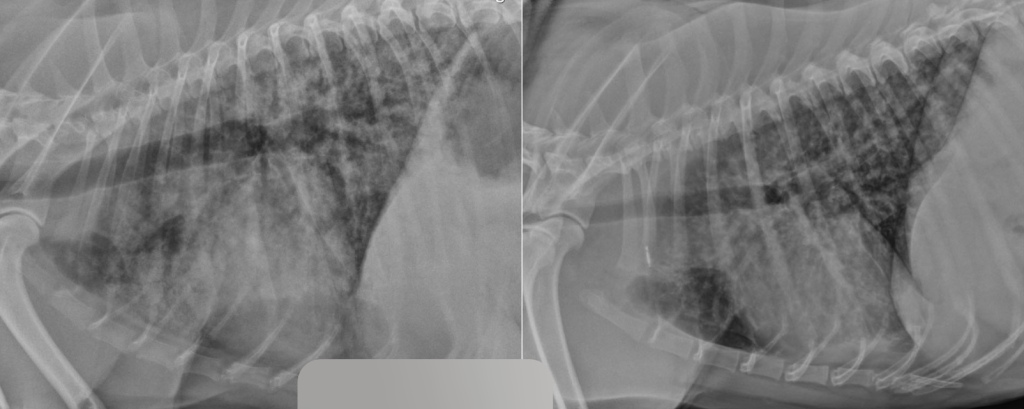

Синдром лептоспирозного легочного кровотечения (англ. leptospiral pulmonary haemorrhage syndrome; LPHS) является тяжелым проявлением острого лептоспироза и в последние годы все чаще диагностируется у собак и других видов животных14. Гистопатологические поражения легочной ткани при LPHS имеют схожие характеристики у разных видов и проявляются различной степенью внутриальвеолярного кровоизлияния при отсутствии выраженного воспалительного клеточного инфильтрата или васкулита. Внутриальвеолярный отек, фибрин и гиалиновые мембраны, характерные для патологий с диффузным альвеолярным повреждением (например, острый респираторный дистресс-синдром; ОРДС), также могут наблюдаться при LPHS, но не являются доминирующими признаками15. Патогенетические механизмы LPHS плохо изучены. В настоящее время исследуются несколько гипотез, включая системные воспалительные, иммуноопосредованные и прямые эффекты, вызываемые лептоспирами. Внутриальвеолярное кровоизлияние может быть обнаружено даже у собак без явных респираторных признаков17. Это указывает на то, что LPHS может быть более распространенным у собак с лептоспирозом, чем принято считать. Рентгенографические изменения, указывающие на LPHS, обычно первоначально проявляются в каудодорсальных отделах легочных полей и, как правило, носят двусторонний и недолевой характер. Поражения варьируются от легкого интерстициального рисунка до легкого или тяжелого ретикулонодулярного легочного рисунка с очаговыми альвеолярными инфильтратами. У некоторых собак наблюдается небольшое количество плеврального выпота (рис. 10). Рентгенографические изменения могут присутствовать даже при отсутствии клинических признаков респираторных нарушений26.